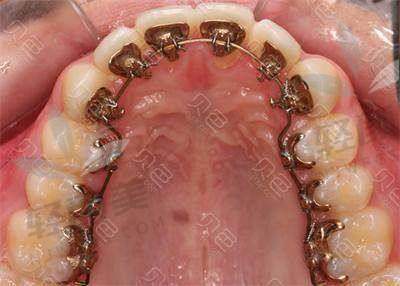

确定好矫正方案后,就开始准备矫正了。首先是安装矫治器,这个过程大概花了一个多小时。医生的手法非常娴熟,动作特别轻柔,虽然在嘴里操作会有点不舒服,但是并没有想象中那么疼。安装好矫治器后,医生还耐心地教我如何清洁牙齿和矫治器,以及一些注意事项。

刚开始戴矫治器的时候,会有点不习惯,说话也会有点大舌头,牙齿还有点酸痛。但是这些不适症状在几天之后就慢慢消失了。在矫正过程中,我每隔一段时间就要去医院复诊一次,医生会根据牙齿的移动情况调整矫治器的力度。每次复诊,医生都会仔细地检查我的牙齿情况,还会和我沟通矫正的进展,让我心里特别踏实。